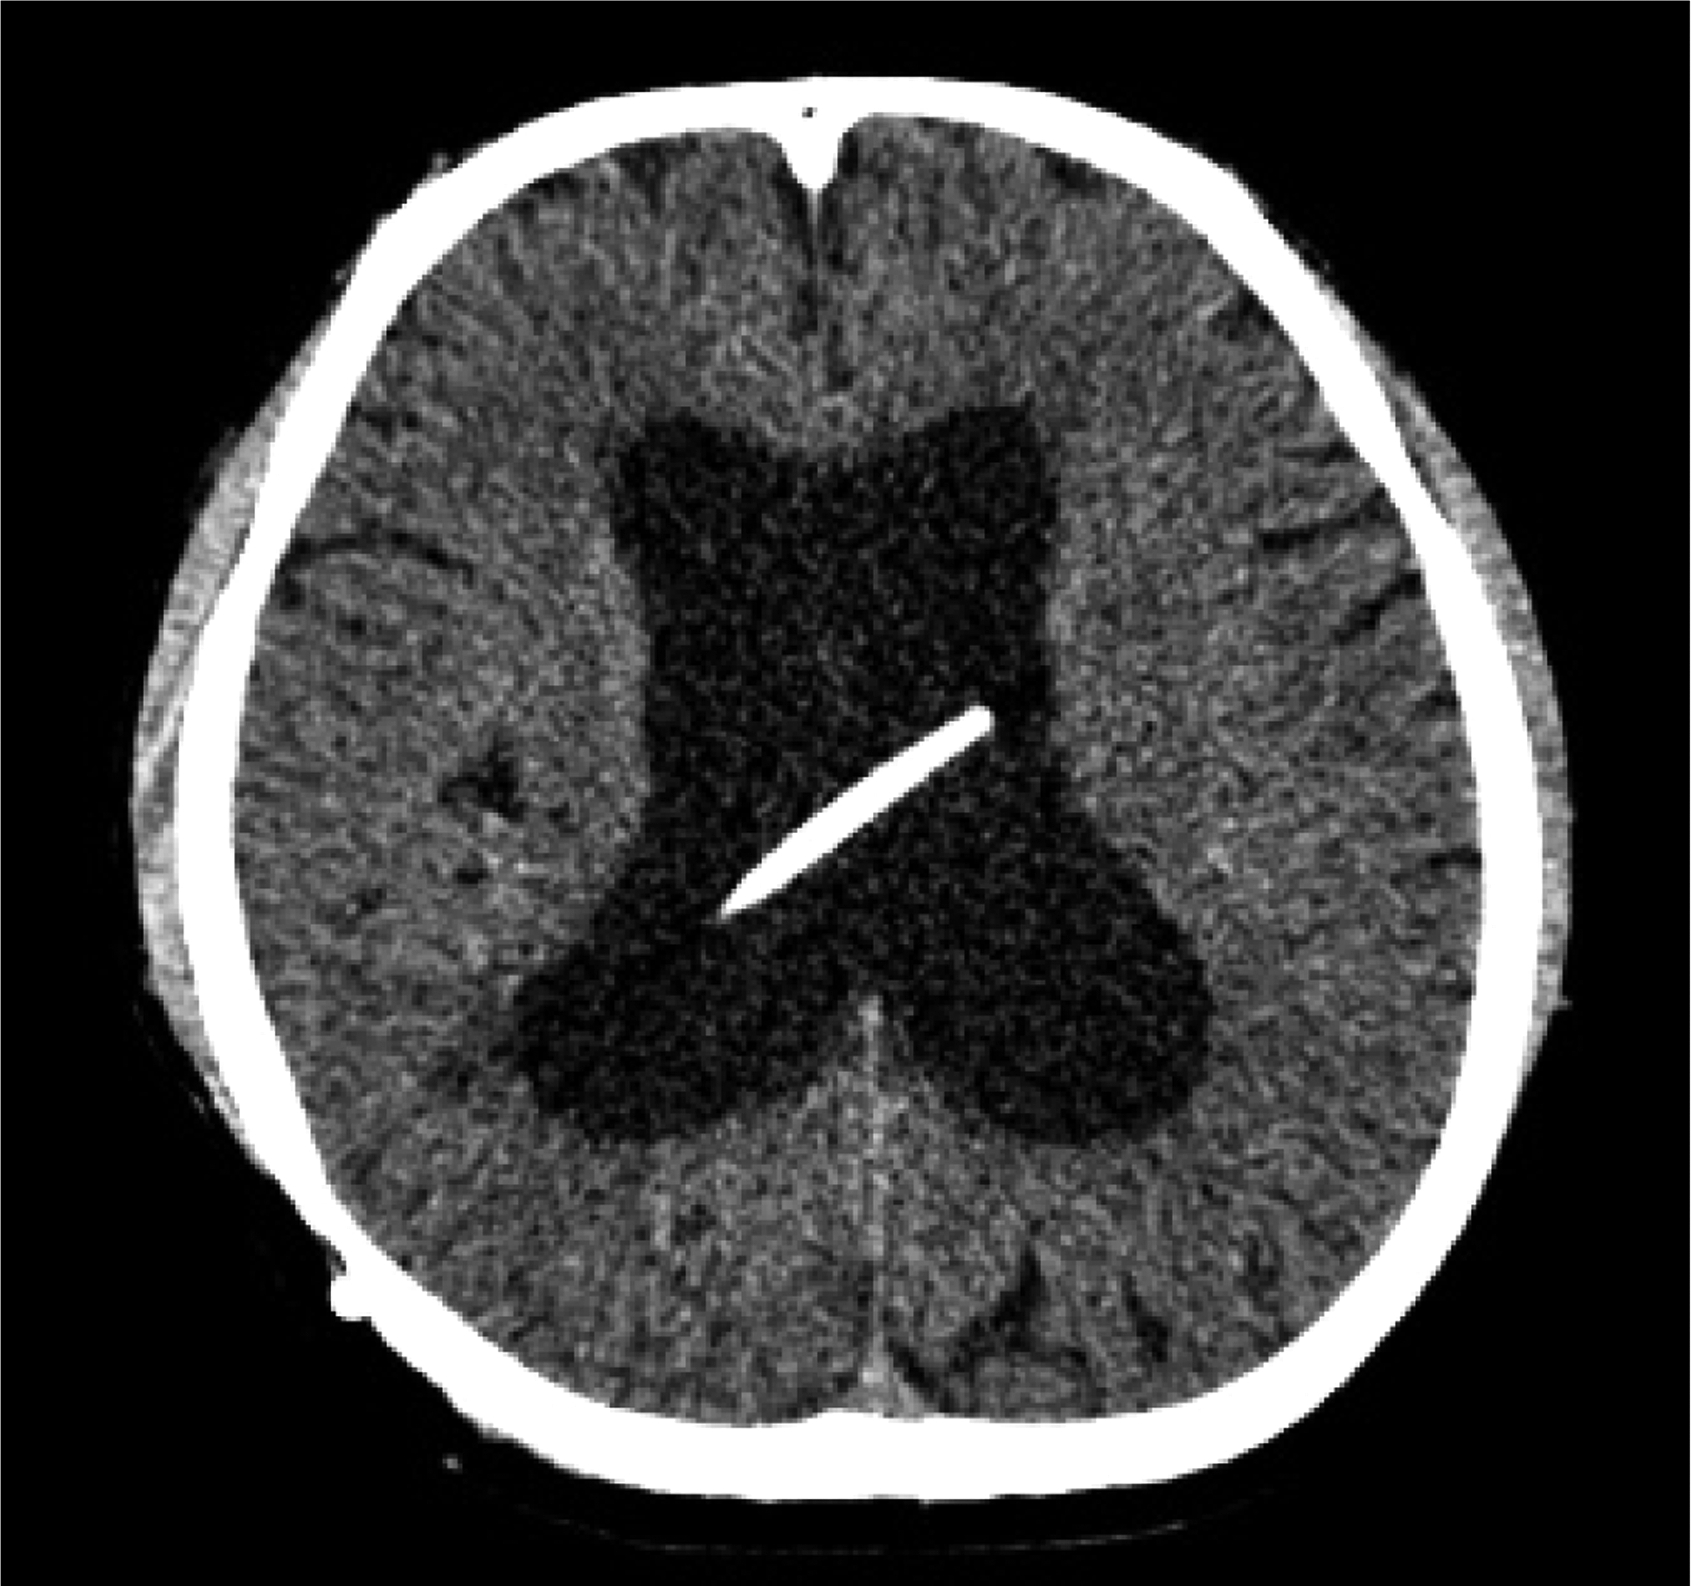

图3-1-1-1 出血后脑积水的脑室演变

a.发病时头颅CT:脑室内血肿呈高密度;b.发病12天后复查CT:血肿已呈低密度;c.发病5个月后头颅MRI:脑室明显扩张,脑室内未见异常信号;d.内镜下探查见脑室内仍有陈旧血斑及含铁血黄素沉积